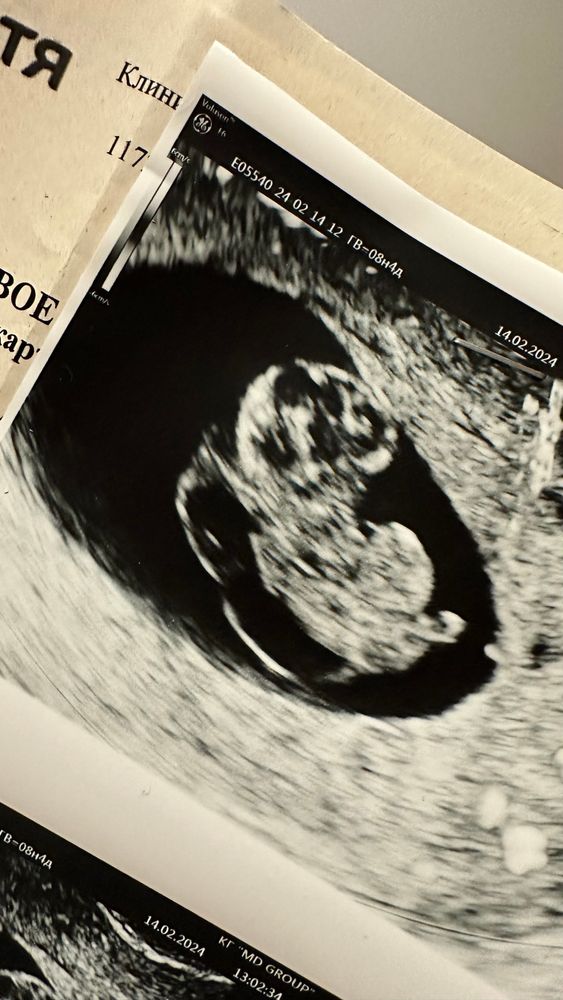

в пятницу еще все было хорошо, ктр 21 мм, чсс 149, через 5 дней ктр 27 мм, а сердцебиения уже нет. Зато есть большой отёк мягких тканей (двойной контур) и гигрома шеи.

У меня была схожая история. Тоже 9 недель , гигрома и отек, появились ещё при наличии сердцебиения. Врач сказал, что все плохо, на контрольном УЗИ уже не было сердцебиения(

Если я правильно вижу то твп большое, хотя многие говорят на него не смотрят на таком сроке, но смотрят нормальные врачи всегда, пгд к сожалению не на всю генетику делают. Очень жаль что так получилось. Держитесь